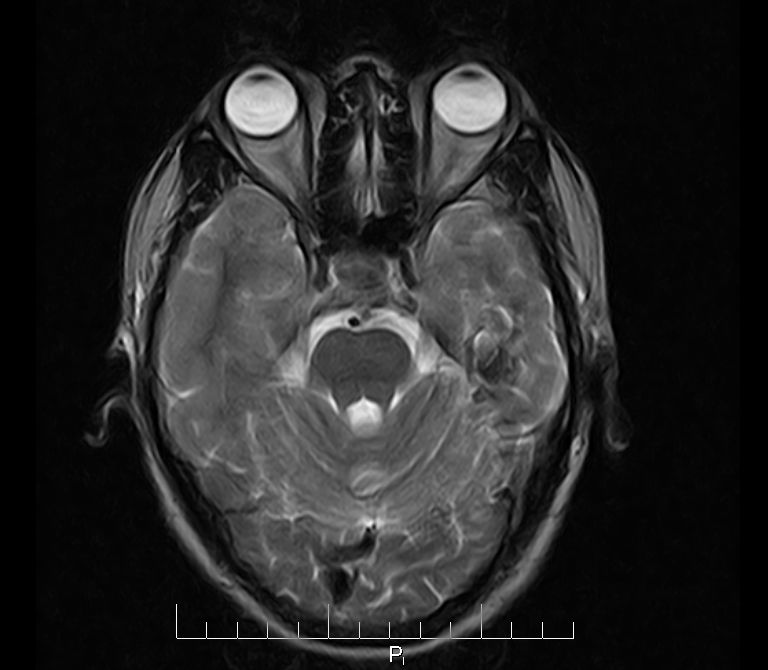

标题: MRI2379:30岁,男,癫痫10年,请各位看一下;CT示:左颞叶钙 [打印本页]

标题: MRI2379:30岁,男,癫痫10年,请各位看一下;CT示:左颞叶钙

左颞叶区见不规则点状混杂信号影

考虑左侧颞叶脑血管畸形(avm)。----t1低等高混杂信号,t2等高信号周边较多流空血管影[冠状位明显],mra左侧大脑中动脉受压,远侧聚集.

考虑avm,建议行增强扫描,看供血a与引流v,以明确诊断。